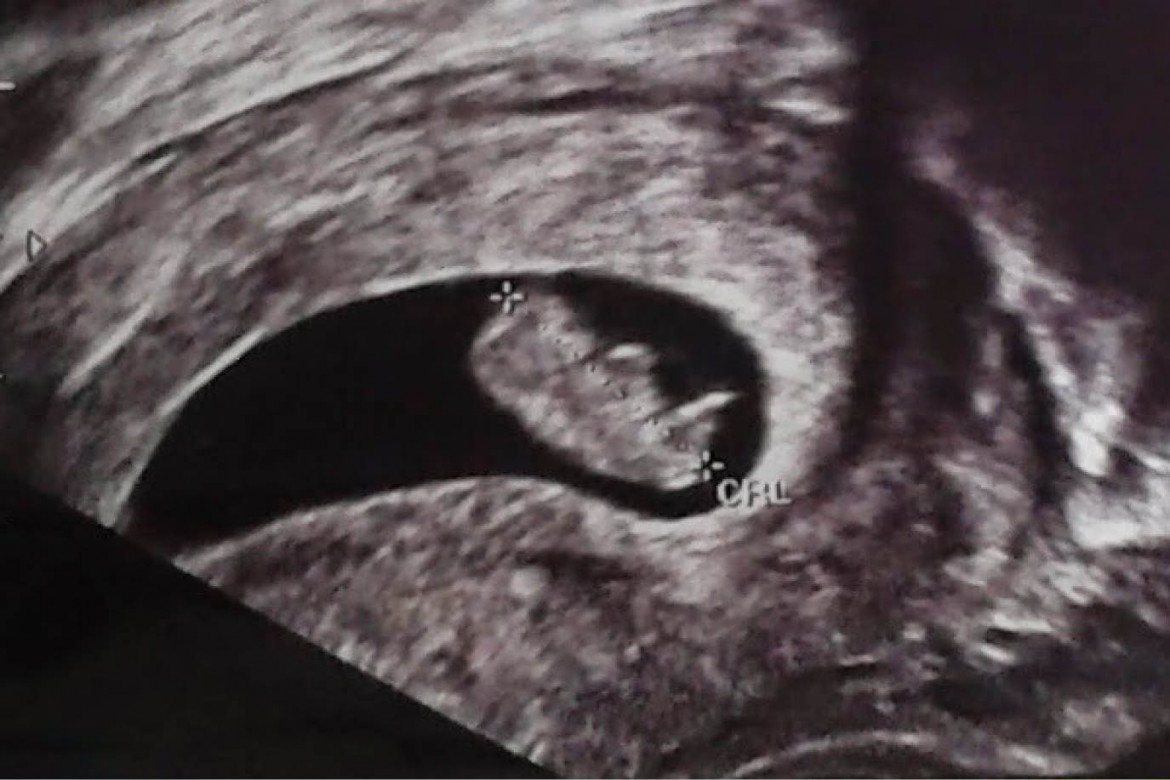

que es una ultrasonografia La ultrasonografía eus ofrece una imagen. La denominación ecografía o ultrasonido se refiere a un procedimiento que emplea ondas sonoras de alta frecuencia para ver el interior del cuerpo, colocando un transductor o. Una ecografía, también conocida como sonograma, es una prueba de diagnóstico por imagen que utiliza ondas sonoras (ultrasonido) para crear imágenes de órganos,. La ultrasonografía es un método de diagnóstico por imagen que utiliza un transductor para emitir. Un ultrasonido de la mama es una técnica de imágenes que se utiliza comúnmente para detectar tumores y otras anomalías en los senos. Aplicaciones en obstetricia y ginecología:. El ultrasonido es un examen médico no invasivo que ayuda a los médicos a diagnosticar y tratar condiciones médicas. Descubre qué es un ultrasonido o ecografía y cuáles son sus usos en el cuidado de la salud.

¿Es malo hacerse muchos ultrasonidos durante el embarazo?